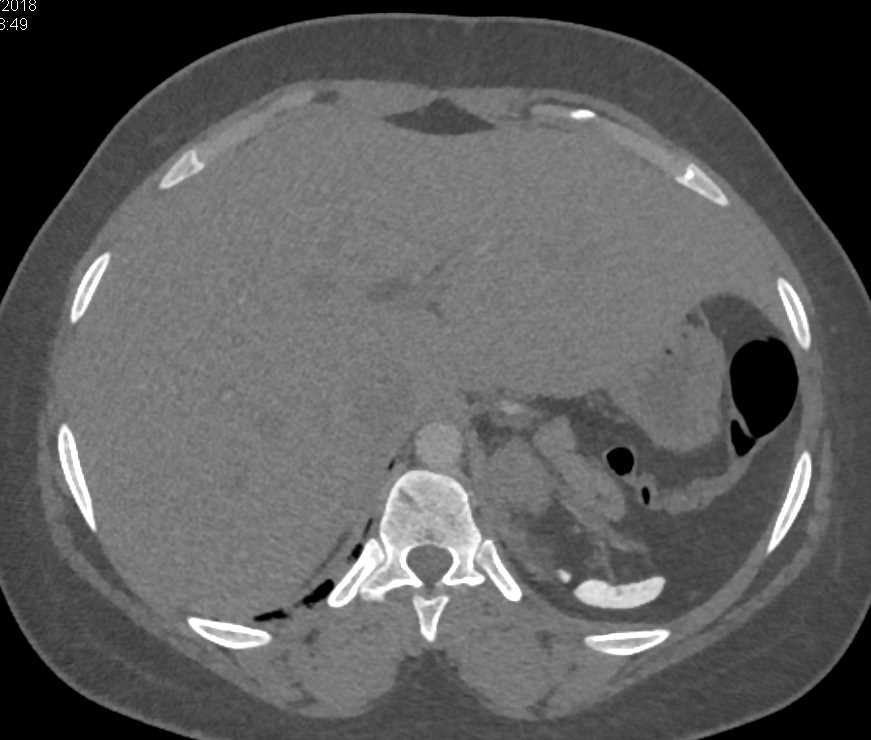

Gaucher's Spleen